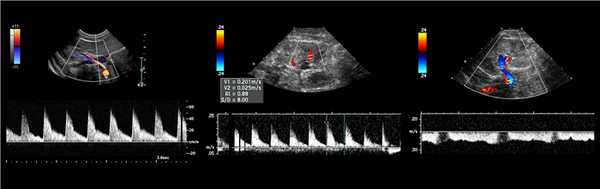

Рисунок. Спектр сосудов почки у новорожденных: почечная артерия — выраженный систолический пик и антеградным диастолический поток (1); высокое сопротивление на внутрипочечных артериях считается нормальным для новорожденных — RI 0,88 (2); почечная вена — поток антеградный с постоянной скоростью на протяжении всего сердечного цикла, минимальные дыхательные колебания (3).